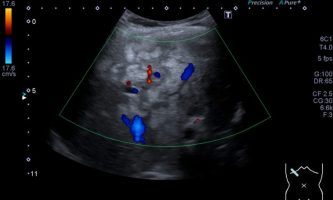

El médico de referencia le indica nueva ecografía de control, donde se observan múltiples y extensas lesiones focales hepáticas hiperecogénicas, redondeadas y confluentes, las cuales predominan en adyacencia a venas supra hepáticas, sin condicionar efecto de masa y sin alteración de la superficie hepática(fig. 1 y 2). Ante la valoración con Doppler color no presenta patrón de flujo peri ni intralesional y respeta el calibre de las venas supra hepáticas(fig. 3 y 4). Dada las características ecográficas se sospecha esteatosis focal multinodular confluente como principal diagnóstico presuntivo, siendo los diagnósticos diferenciales patologías de naturaleza infecciosa, tumoral o metastásica.